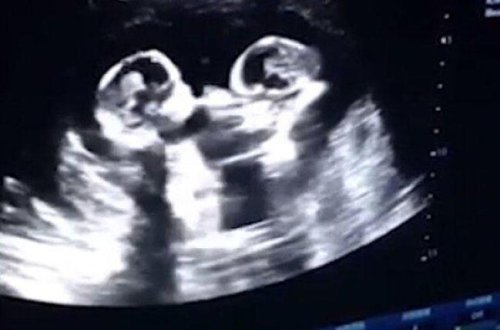

Ana bətnindəki əkizlərin bir-birinə etdiyi bu hərəkət hamını ŞOKA SALDI -

İNANILMAZ - VİDEO